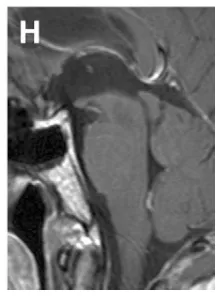

(H)术后2年经幕下小脑上入路全切肿瘤后矢状位T1增强MRI,示肿瘤全切除,患者无神经功能缺损,恢复良好。